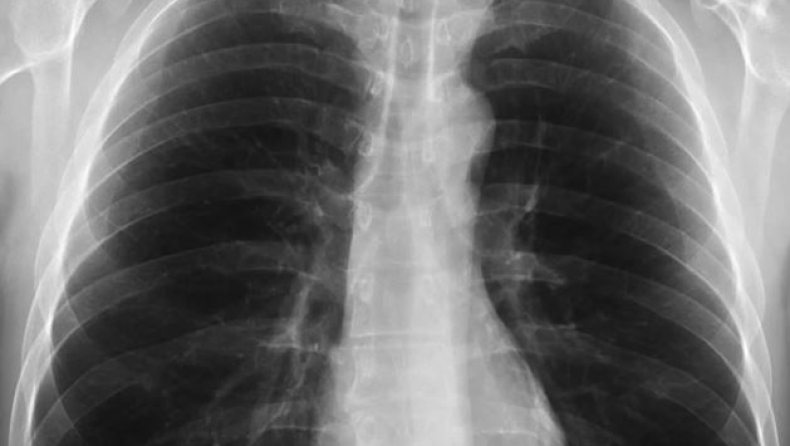

Χαρακτηρίζεται περιπατητική πνευμονία ή σύνδρομο του λευκού πνεύμονα γιατί στην ακτινογραφία του ασθενούς ο πνεύμονας φαίνεται σαν αν είναι λευκός. Τα συμπτώματα περιλαμβάνουν πονόλαιμο, κόπωση και παρατεταμένο βήχα που μπορεί να διαρκέσει για εβδομάδες ή και μήνες.

«Ο λευκός πνεύμονας αναφέρεται στην ακτινολογική απεικόνιση ορισμένων πνευμόνων και αντί να μαυρίζει η ακτινογραφία, έχουμε διηθήματα. Αν αυτά εμφανιστούν σε μεγάλη έκταση του πνεύμονα – ιδιαίτερα όταν υπάρχει αυτό που λέμε σύνδρομο αναπνευστικής δυσχέρειας, που γεμίζουν σχεδόν όλες τις κυψελίδες με υγρό – τότε σχηματίζεται μια λευκή εικόνα αντί το μαύρο που περιμένουμε στο φυσιολογικό και έτσι κατ ευφημισμόν ονομάστηκε εικόνα λευκού πνεύμονα» εξήγησε αναλυτικά ο καθηγητής Πνευμονολογίας της Ιατρικής Σχολής του Πανεπιστημίου Κρήτης, Νίκος Τζανάκης, μιλώντας στην ΕΡΤ, ενώ παράλληλα τόνισε πως αυτό το στοιχείο μπορεί να παρουσιαστεί σε όλες τις πνευμονίες, ανεξαρτήτως αιτίας.